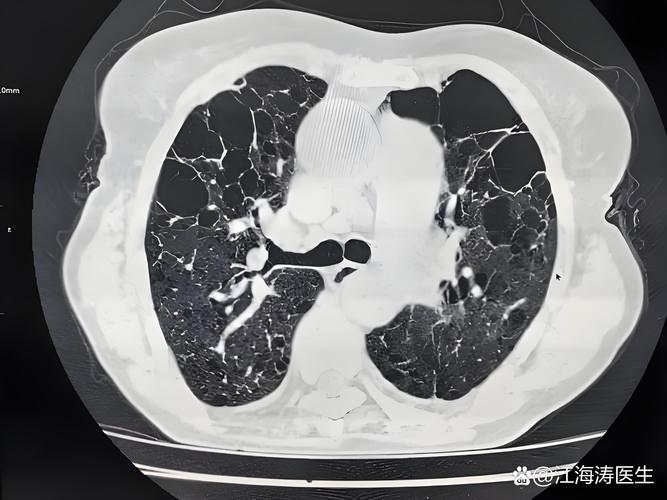

肺部感染

- 核心问题: 病原体(细菌、病毒、真菌等)侵入肺部,引起肺泡和肺间质的炎症。

- 常见类型: 支气管炎、肺炎,社区获得性肺炎和医院获得性肺炎都很常见。

- 常见原因: 身体免疫力下降、误吸(食物、口水)、长期卧床等。

- 典型症状:

- 咳嗽、咳痰: 痰液可能呈脓性、铁锈色或带血。

- 发热、寒战。

- 胸痛: 咳嗽或深呼吸时加重。

- 呼吸困难、气促。

- 关键点: 对于有基础病(如肺气肿、心梗、脑梗后卧床)的患者,肺部感染是极其危险的并发症,是导致病情加重甚至死亡的重要诱因。

肺气肿

- 核心问题: 一种慢性阻塞性肺疾病(COPD)的主要类型,肺泡(肺部进行气体交换的小泡)的结构被破坏,导致肺过度充气,弹性回缩力下降。